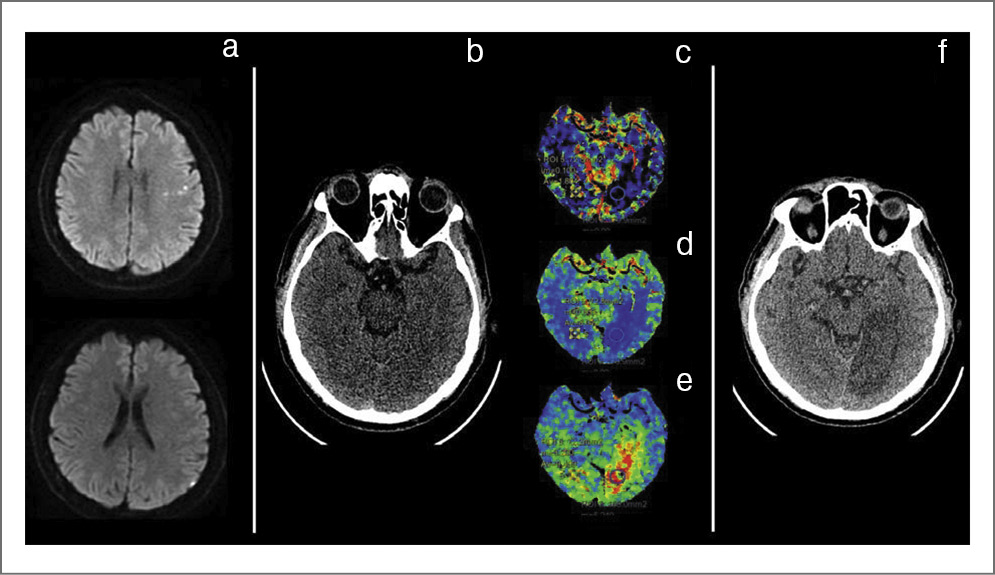

Пациент 63 лет в 2020 г. перенес ИИ в бассейне левой средней мозговой артерии (рис. 1, a, диффузионная магнитно-резонансная томография) с полным регрессом неврологического дефицита. При обследовании выявлена пароксизмальная форма ФП, назначен ПОАК, который пациент не принимал. Внезапно 21 марта 2022 г. возникло нарушение зрения и неловкость в правой руке. Поступил в стационар через 12 ч от момента развития симптомов, NIHSS 2 балла (гемианопсия). Выполнена компьютерная томография (КТ) головного мозга (рис. 1, b, видны ранние признаки ишемии в бассейне левой задней мозговой артерии) и перфузионная КТ (рис. 1, с, – объем мозгового кровотока, рис. 1, d, – скорость мозгового кровотока, рис. 1, e, – максимальное время транзита контрастного препарата). Внутривенный тромболизис не проводили из-за неблагоприятного перфузионного профиля. Поскольку при первичной визуализации выявлена формирующаяся зона инфаркта достаточно большого размера, выполнена контрольная КТ (рис. 1, f) через 1 сут. Визуализирован инфаркт размером более 5 см с ГТ по типу геморрагического инсульта 1-го типа. Принято решение назначить апиксабан в дозе 5 мг 2 раза в день на 14-е сутки.

Рис. 1. Клинический пример назначения ПОАК в остром периоде КЭИ.